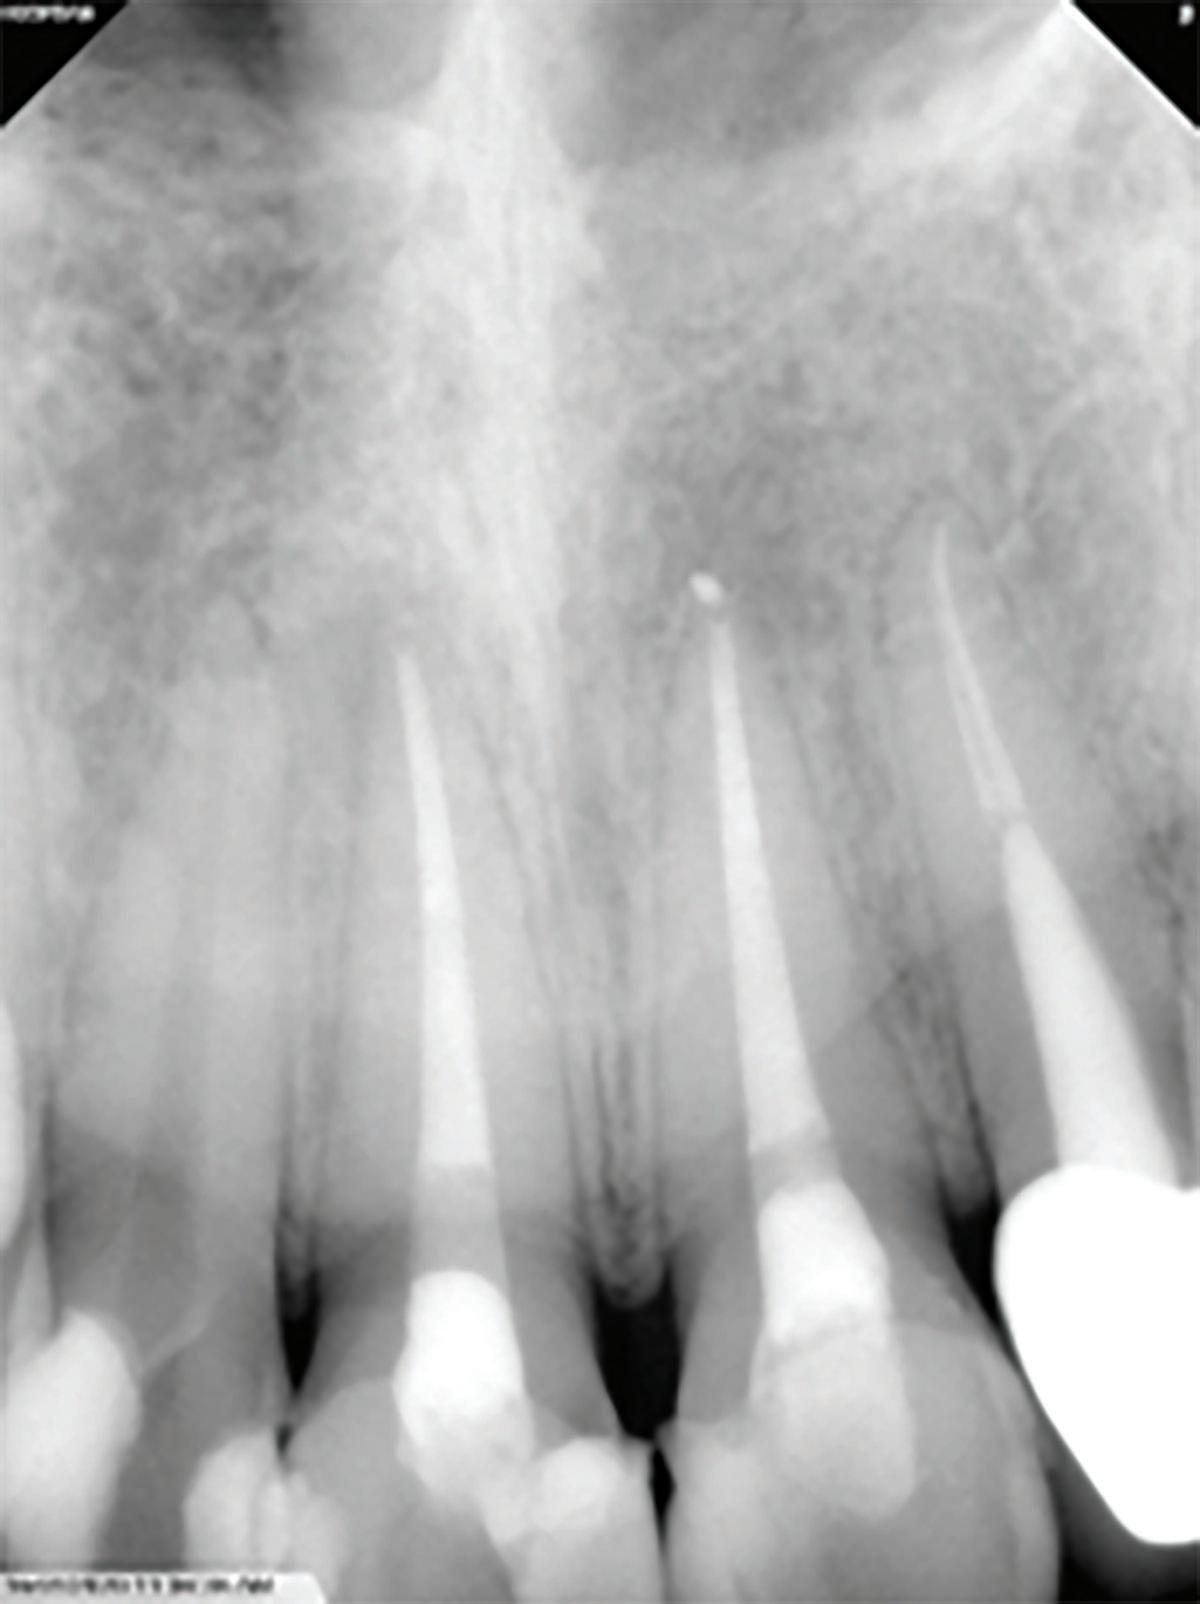

Imaging tools to identify anatomical risk Periapical radiography

Proper diagnosis is essential to identifying cases at risk of extrusion. Conventional periapical radiography remains a fundamental diagnostic tool in endodontics, offering high-resolution, real-time imaging at low radiation exposure and minimal cost. However, the 2-dimensional (2D) nature of periapical radiographs presents inherent limitations when complex root anatomy is evaluated, especially in the apical third.

One of the most significant shortcomings of periapical radiography is its inability to provide information in the buccolingual dimension. This makes it difficult to detect resorptive lesions (internal or external) located on the buccal or lingual surfaces; fenestrations or dehiscences in the cortical plate; split canals, C-shaped canals, or isthmuses hidden in a single projection; and superimposed anatomical structures, including the zygomatic arch over maxillary molars or mental foramen overlapping premolar apices.

To improve diagnostic accuracy, clinicians are encouraged to take multiple angulated views. However, even with angulated views, the 2D limitation persists, and structures with significant buccolingual spread or overlap may still be misinterpreted. In cases in which a patient’s symptoms persist despite normal

Fig 2. Calcium hydroxide extrusion. During treatment of the mandibular left first molar, dysesthesia (burning pain) and paresthesia resulted from a substantial overfill of calcium hydroxide into the inferior alveolar nerve canal. (Courtesy of

radiographic findings, or an apical resorption, a fenestration, or an anatomical anomaly is suspected, reliance on periapical radiographs alone may result in missed diagnoses or mismanagement (Fig 4).

Additionally, periapical radiographs may underestimate the extent of periapical bone loss or resorption if confined to the cortical plate or masked by trabecular density. For instance, studies have shown that periapical radiolucencies must involve at least 30% mineral loss in the bone to be radiographically visible.24,25